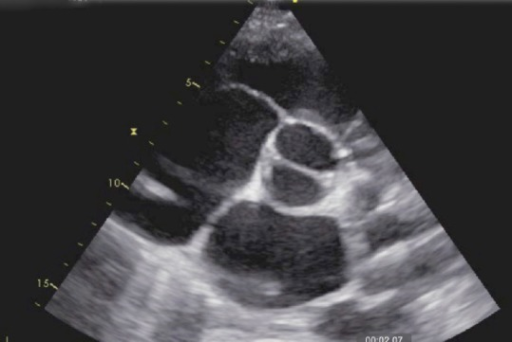

Puzzle 42

What's the Diagnosis?